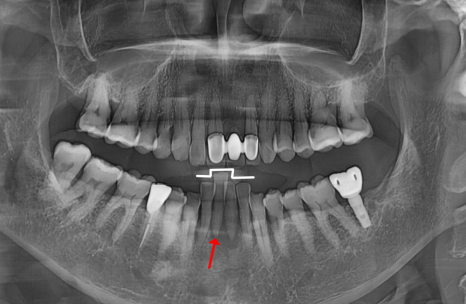

221022

발치보다는

살릴 방법부터 고민합니다.

솟구치는 앞니, 흔들리는 치아가 보내는 '이 신호' 무시하면 안 되는 이유

'자연치아 지키기'에 진심인 저는

이번 환자분의 진단 결과 앞에서

고민이 참 많았습니다.

가운데 2개는 발치가 불가피했지만,

양옆 치아들은 제법 든든하게

제자리를 지키고 있었기 때문입니다.

230602

다만 전체적으로 낮아진 잇몸뼈가

마음에 걸려,

환자분께 두 가지 선택지를

상세히 설명해 드렸습니다.

자연치아를 최대한 살릴 수 있지만

남은 치아에 무리가 갈 수 있는 '브릿지'와,

아쉽지만 옆 치아까지 정리해

염증의 원인을 근본적으로 해결하는

'임플란트'였습니다.